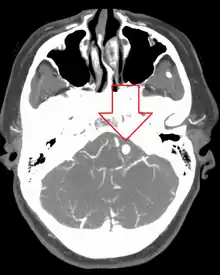

Diagnosis of a ruptured cerebral aneurysm is commonly made by finding signs of subarachnoid hemorrhage on a computed tomography (CT) scan. If the CT scan is negative but a ruptured aneurysm is still suspected based on clinical findings, a lumbar puncture can be performed to detect blood in the cerebrospinal fluid. Computed tomography angiography (CTA) is an alternative to traditional angiography and can be performed without the need for arterial catheterization. This test combines a regular CT scan with a contrast dye injected into a vein. Once the dye is injected into a vein, it travels to the cerebral arteries, and images are created using a CT scan. These images show exactly how blood flows into the brain arteries.[39]